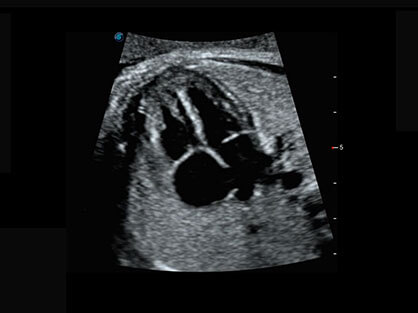

微米成像技术提升了对组织斑点噪声信号的抑制能力,并进一步强化边界信息,从而获得清晰图像。

0.5mm厚度的薄层切片显像,可清晰显示微小病灶的连续断面。

可同时显示组织结构表面和内部的轮廓信息,达到透视效果,为临床提供更丰富的诊断信息。